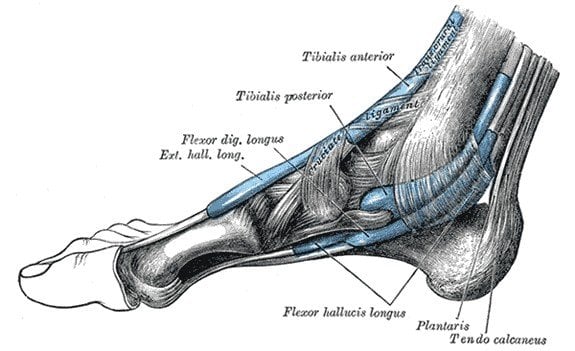

6. Plantaris Muscle

We used these muscles to grip objects using just our feet, which came in ‘handy’ when we were busy eating a banana with one hand and hanging onto a branch with another. Humans still have this muscle, but it is about as useful as Justin Bieber. Doctors actually take tissue from this muscle for reconstruction surgery in other parts of the body, so we at least get some use out of these features, which is more than we can say about Bieber Fever.